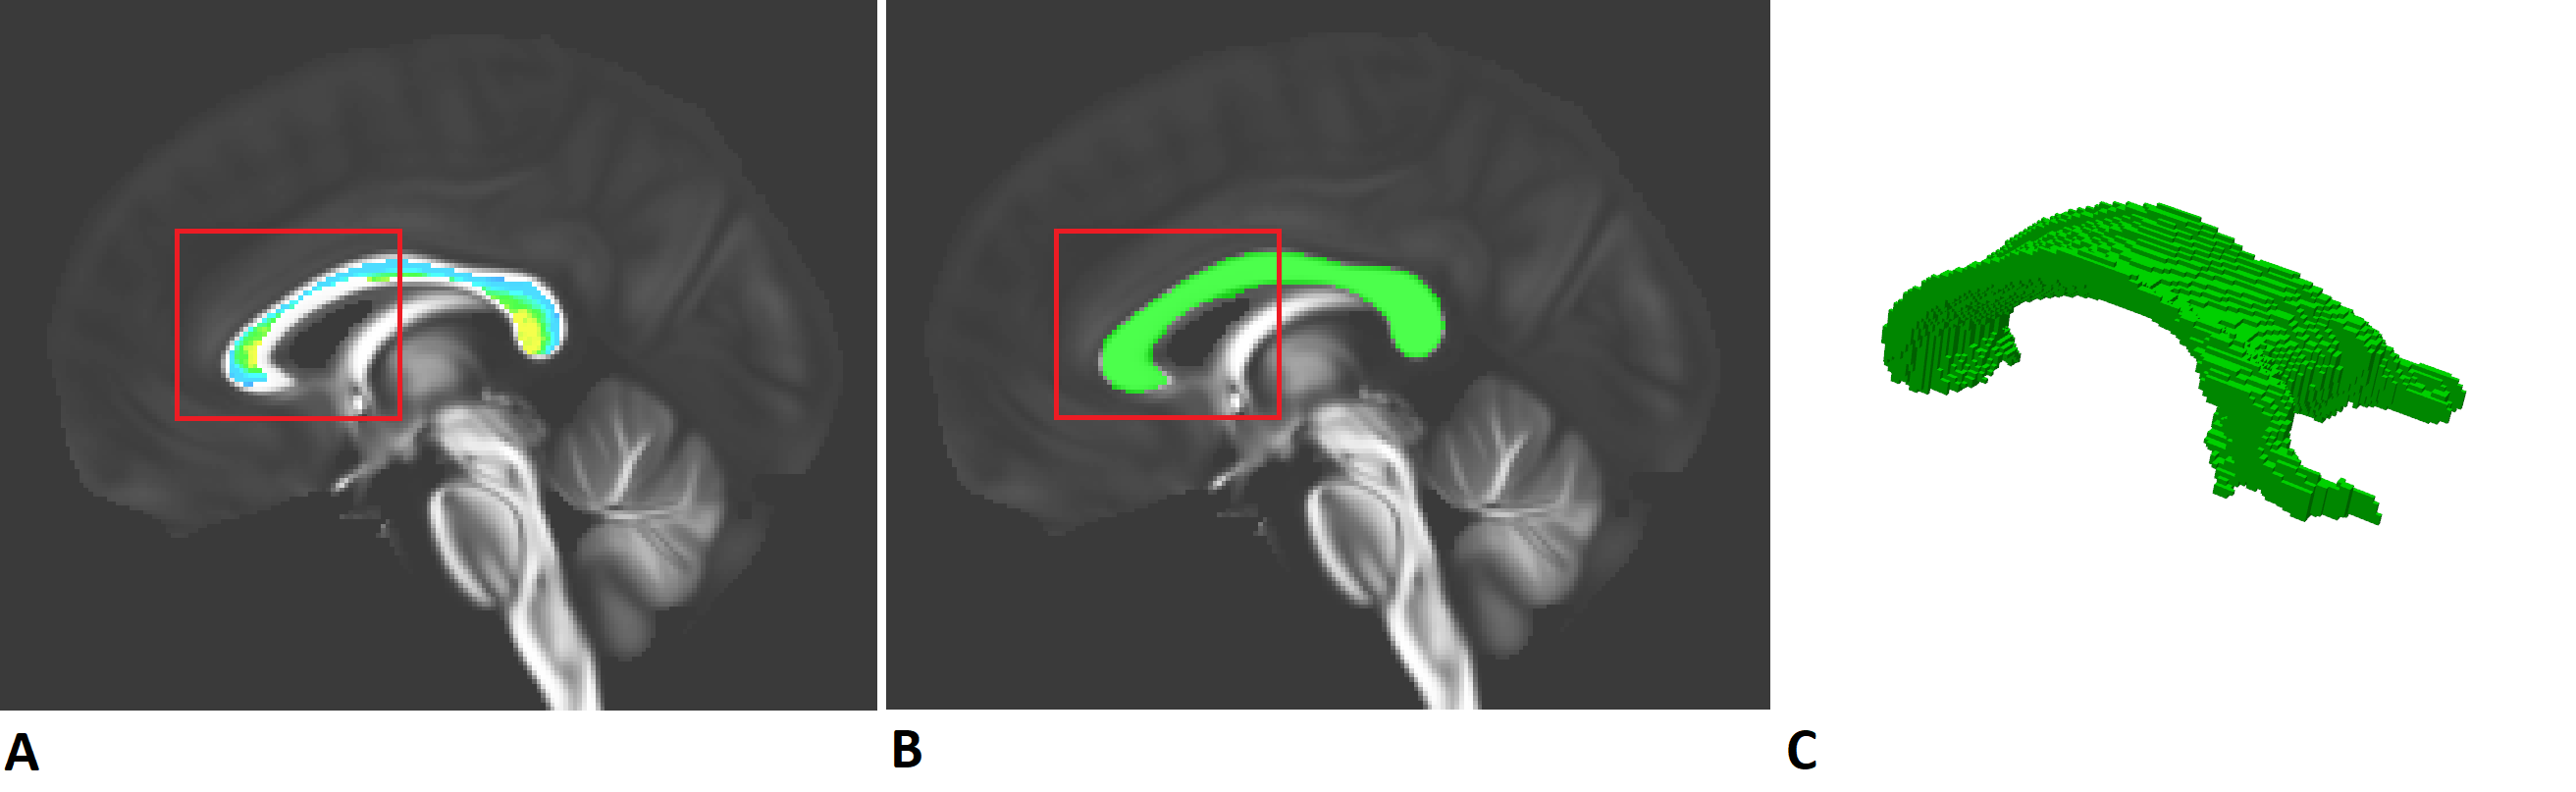

7. Corpus_callosum_reg.py: This is the code corresponding to the creation of our CC. As we can see on the following image, the downloaded Corpus Callosum was not of good quality (Fig A.) so we drew it ourselves (thanks to MRIcron) as depicted in Fig B. and its 3D representation (Fig C.). However, you don't need the registration_CC_on_perfect function and the last part of this file (MASK FA). You will only need to resubmit the reg_CC_on_sub if you have new patients.